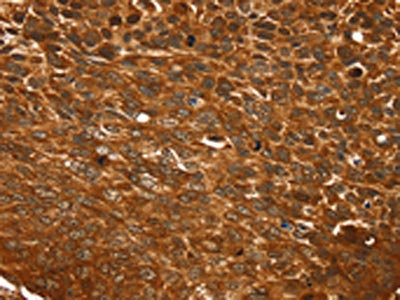

The image on the left is immunohistochemistry of paraffin-embedded Human esophagus cancer tissue using CSB-PA069259(TCEB3B Antibody) at dilution 1/25, on the right is treated with synthetic peptide. (Original magnification: ×200)

The image on the left is immunohistochemistry of paraffin-embedded Human lung cancer tissue using CSB-PA069259(TCEB3B Antibody) at dilution 1/25, on the right is treated with synthetic peptide. (Original magnification: ×200)